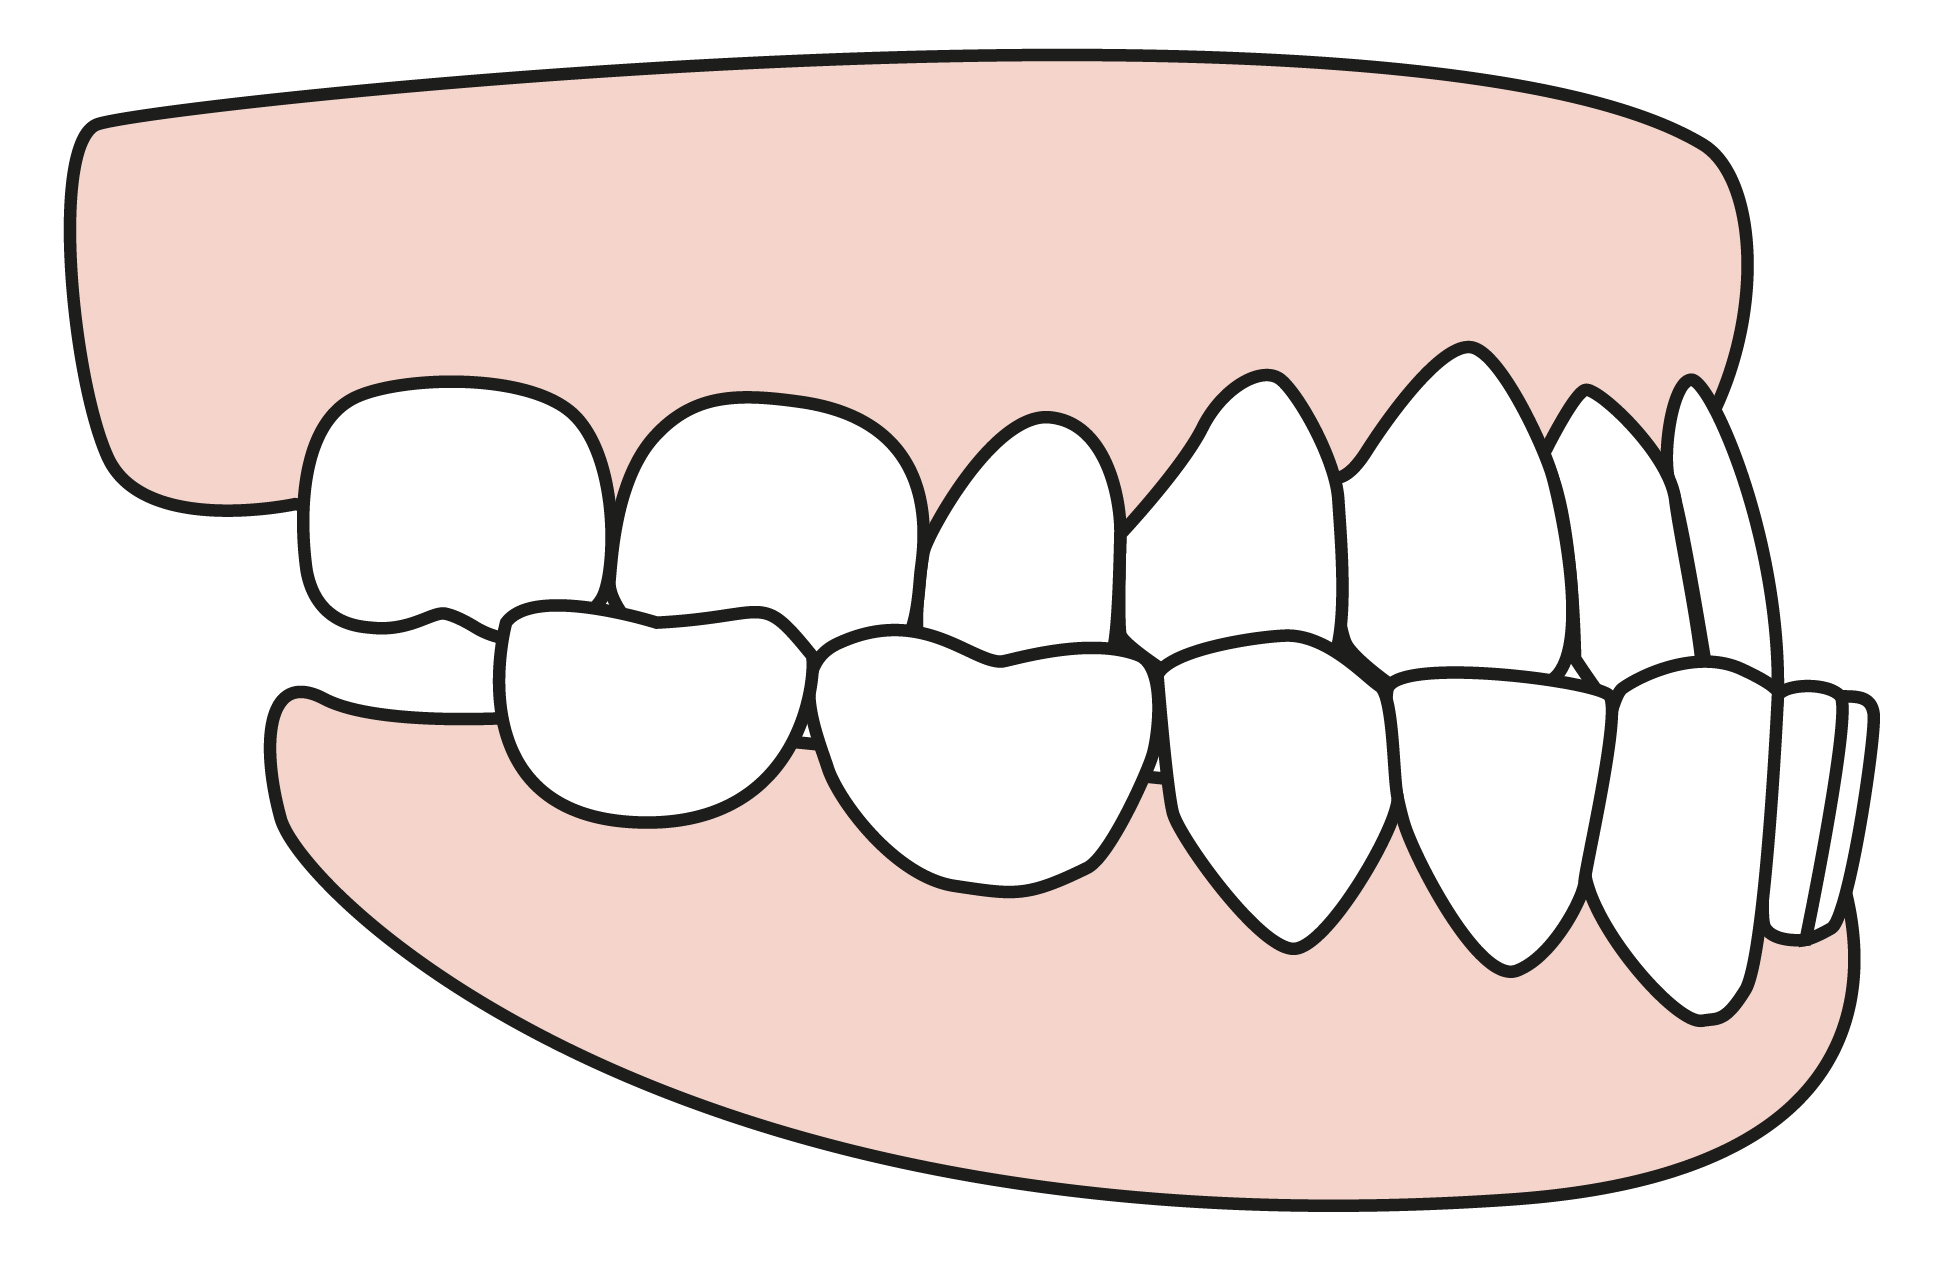

DO YOU HAVE DENTURES?

Do you have cosmetic or restorative work done?

How many teeth are you missing?

Do you an overbite or underbite?

Do you have tooth decay?

Do you have periodontal disease?

Do you have bruxism?

Do you have TMJ?

Do you have allergies to acrylic or stainless steel?

Taking Impressions

Taking Impressions

Taking Impressions

Taking Impressions

Taking Impressions

Taking Impressions

Taking Impressions

Taking Impressions

Taking Impressions

Taking Impressions

Taking Impressions

Taking Impressions

Taking Impressions

Taking Impressions

Taking Impressions

Taking Impressions

Taking Impressions

Taking Impressions

Taking Impressions

Taking Impressions

Taking Impressions